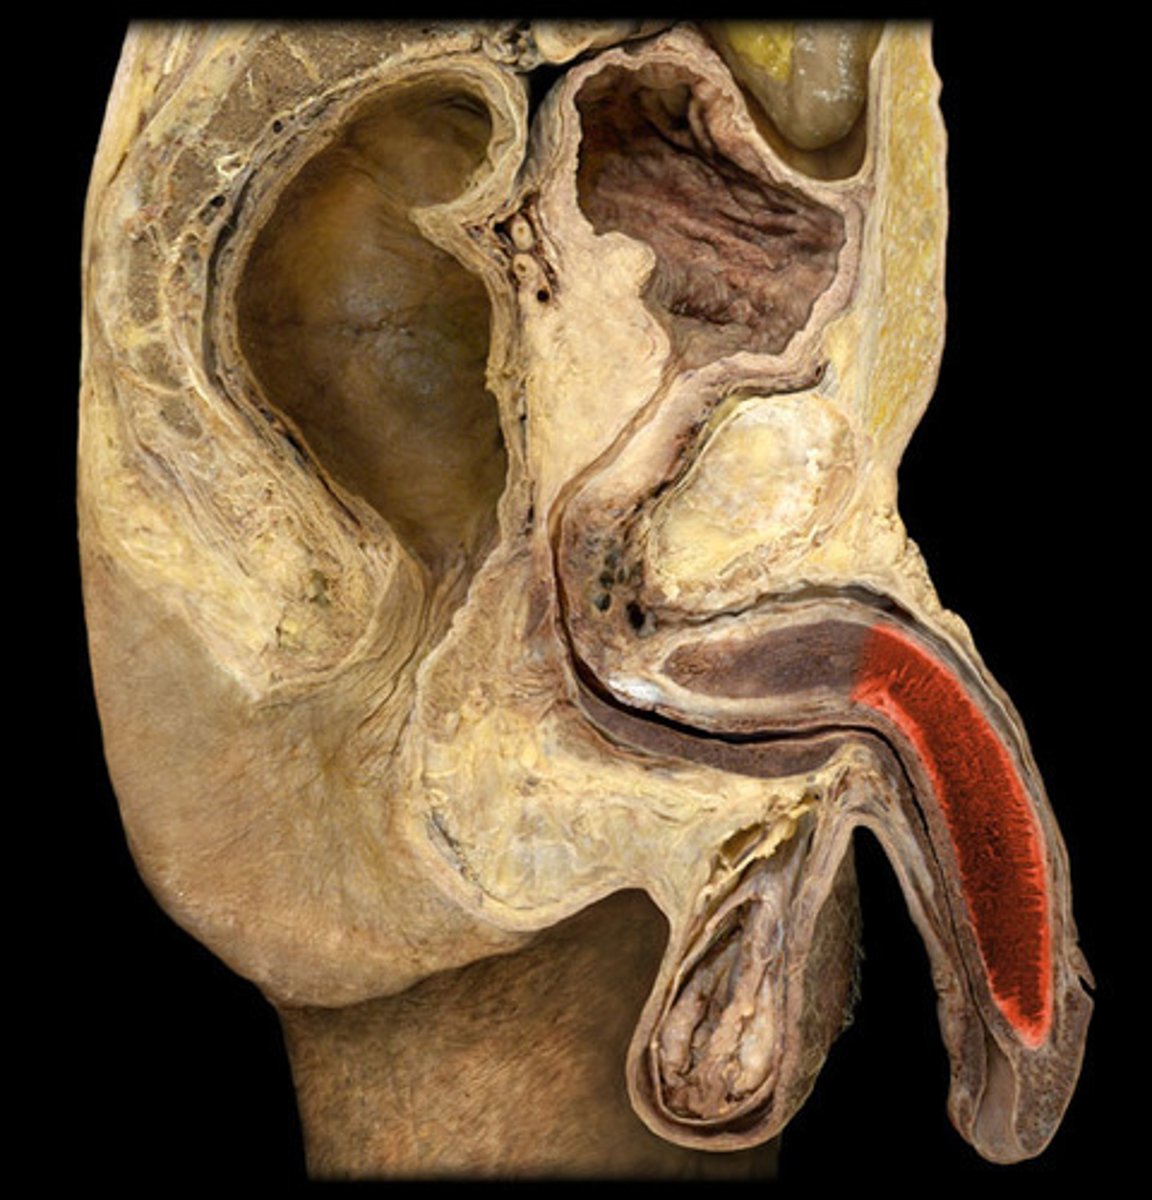

Testis

Epididymis

Spermatic Cord

Vas Deferens

Seminal Vesicle

Prostate

Penis

Corpus Cavernosum

Glans Penis